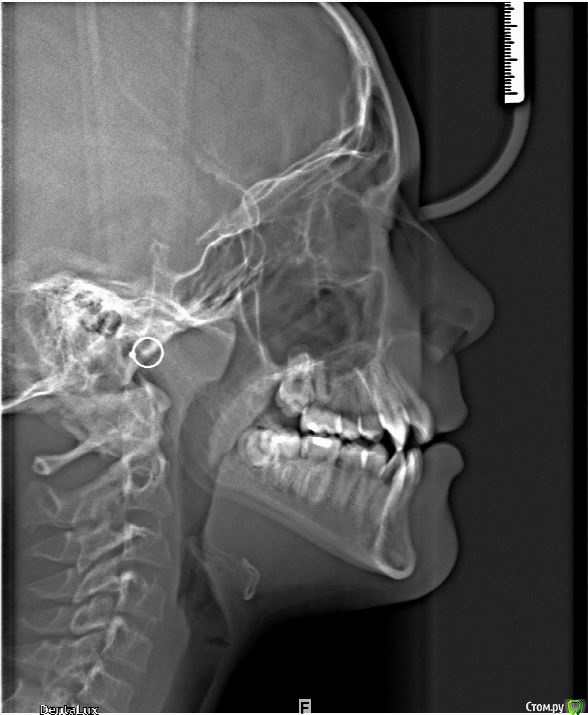

Алевтина Петровна Опубликовано 28 августа, 2015 Автор Поделиться Опубликовано 28 августа, 2015 На курсах разбирали стадии роста по ТРГ, по позвонками, дак по моему очень даже можно получить скелетный эффект. Ну по крайней мере я на это надеюсь. Ссылка на комментарий

Maverick Опубликовано 29 августа, 2015 Поделиться Опубликовано 29 августа, 2015 Хайрекс вплоть до 15 лет дает хороший скелетный эффект. Никакого хирурга не надо. Зачем простое занятие превращать в травматичное, да и порой на которое родители не дают согласие. Мальчик такого возраста отличный пациент для скелетного расширения верхней челюсти. Как вариант посмотреть по позвонкам на трг на скелетный возраст , а судя по его трг, у него он еще есть. Так что вам ничего не мешает работать. Ссылка на комментарий

Maverick Опубликовано 29 августа, 2015 Поделиться Опубликовано 29 августа, 2015 А зубы и их прорезывание, а также состояние верхушек не показатель. 1 Ссылка на комментарий